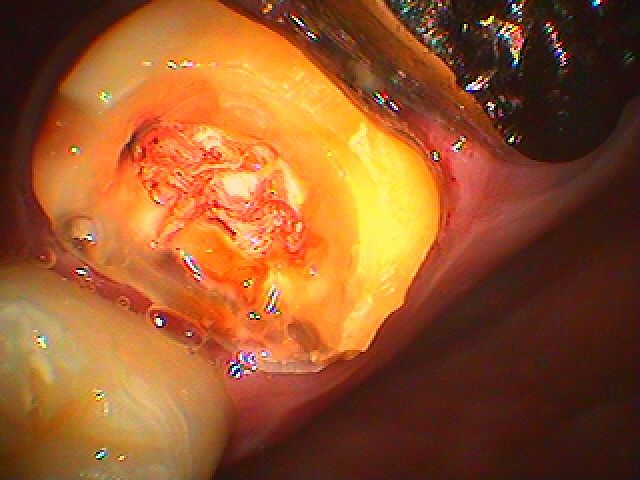

根の治療からのセラミック治療へ。 被せを入れる際にはどんな歯でも根の治療をしなおし、その歯が割れていたり将来、化膿して来たりしないようにしています。| |広島市安佐南区の歯科医院 根の治療からのセラミック治療へ。 被せを入れる際にはどんな歯でも根の治療をしなおし、その歯が割れていたり将来、化膿して来たりしないようにしています。 トップ お知らせ・ブログ 根の治療からのセラミック治療へ。 被せを入れる際にはどんな歯でも根の治療をしなおし、その歯が割れていたり将来、化膿して来たりしないようにしています。 根の治療からのセラミック治療へ。 被せを入れる際にはどんな歯でも根の治療をしなおし、その歯が割れていたり将来、化膿して来たりしないようにしています。 Web診療予約 初めての方へ 選ばれ続ける理由 院内設備について 歯が痛いしみる一般歯科 歯がぐらぐらする歯周病 健康な歯を保ちたい予防歯科 子供の虫歯予防をしたい小児歯科 銀歯をセラミックに審美歯科 白い歯を目指しませんか?ホワイトニング 矯正専門医がいるので安心矯正歯科 抜けた歯を補いたいインプラント・入れ歯 医院案内 スタッフ紹介 メリィハウス歯科クリニックオフィシャルホームページ ラベンダー歯科クリニックオフィシャルホームページ お知らせ・ブログ ホーム 診療科目 一般歯科 歯周病治療 予防治療 小児歯科 審美治療 ホワイトニング 矯正歯科 入れ歯・インプラント マウスピース矯正 初めての方へ 院長・スタッフ 設備紹介 医院案内・アクセス メニューを閉じる